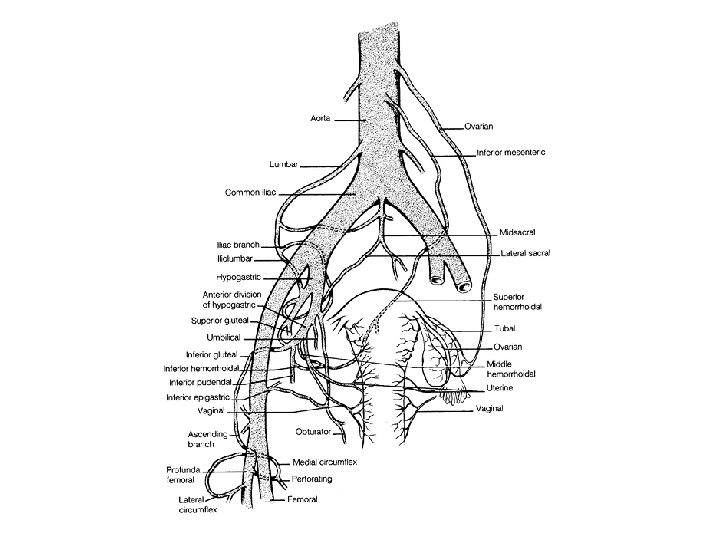

Pelvic Vasculature Sakralis Media İnternal iliak (hipogastrik) Common Iliac İliolumbar Lateral Sakral Superior Gluteal Inferior Gluteal Orta Hemoroidal Pudendal Uterin Inferior Vesika Umbilical Obturator Burnett Novack’s Gynecology 20

Branches of the Internal Iliac Artery Anterior Division Posterior Division Uterine Umbilical Uterine vesical Obturator Internal pudendal Inferior gluteal Middle vesical Middle rectal Vaginal Superior gluteal Lateral sacral Iliolumbar

• Ovarian arteries – Originate directly from the aorta, inferior to the renal arteries. – Most frequently identified at the IP ligament. • Ovarian veins: – Left ovarian vein drains into the left renal vein – Right ovarian vein drains directly into the inferior vena cava.